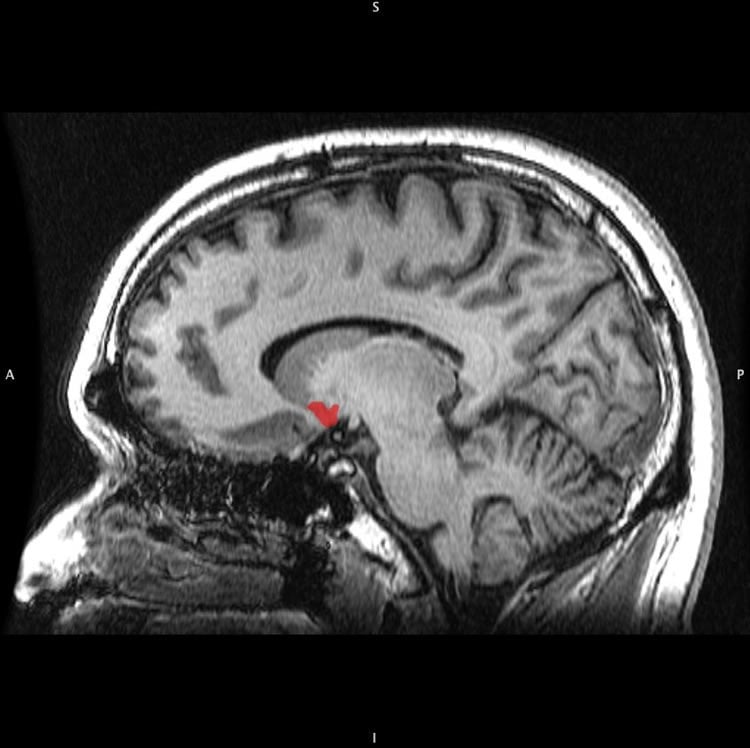

Close collaboration between Rauschecker’s lab and PainLabMunich, led by TUM Prof. Markus Ploner, has extended this research into the common ground that tinnitus shares with chronic pain. And that common ground now has an address in the brain. Structural and functional changes in the same brain circuit – including the ventromedial prefrontal cortex and the nucleus accumbens – can open the gateway to both tinnitus and pain that persists long past any acute cause.

In their new paper Rauschecker and Ploner, together with postdoctoral researchers Audrey Maudoux (Georgetown) and Elisabeth May (TUM), present copious evidence that similar structures and functional systems are involved in tinnitus and chronic pain and probably play a central role in both. Significant loss of gray matter and compromised circuit function are observed in the suspected regions, with considerable overlap between neurological changes in tinnitus and chronic pain sufferers.

All of these areas are also important for evaluating and modulating emotional experiences, Rauschecker says. “These areas act as a central gatekeeping system for perceptual sensations, which determines the affective value of sensory stimuli – whether produced externally or internally – and modulates information flow in the brain. Tinnitus and chronic pain occur when this system is compromised.”

The researchers propose that this newly identified gatekeeping system determines the relevance and affective value of sensory stimuli and controls information flow along pathways associated with the so-called executive functions. The process, they say, is controlled by two major neurotransmitters, dopamine and serotonin. Damage to this system, they argue, affects the perception of sensory signals in such a way that either tinnitus or chronic pain can develop and carry on in a self-perpetuating loop.